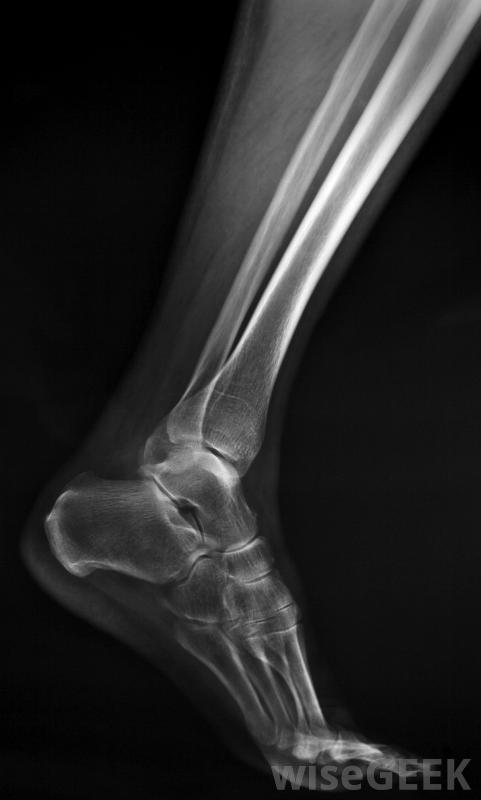

胫骨、腓骨和距骨组成踝关节。踝关节由胫骨、腓骨和距骨组成,距骨上有三条韧带:距骨腓骨韧带,前后韧带,以及跟腓骨韧带。这些骨和韧带一起构成了踝关节